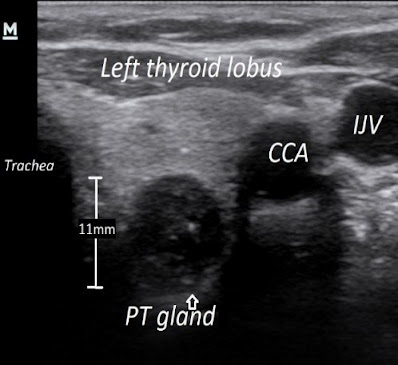

Ukoliko je ipak vrednost alkalne fosfataze (surogat

markera za metabolizam kostiju) normalna, a paratireodine žlezde na pregledu

ultrazvukom ne prelaze 1cm u prečniku, još uvek je moguće postići remisiju ovog

stanja medikamentoznom terapijom. Na slici br. 4 je primer ultrazvučnih prikaza uvećanih

paratireoidnih žlezdi kod jednog pacijenta na dijalizi.